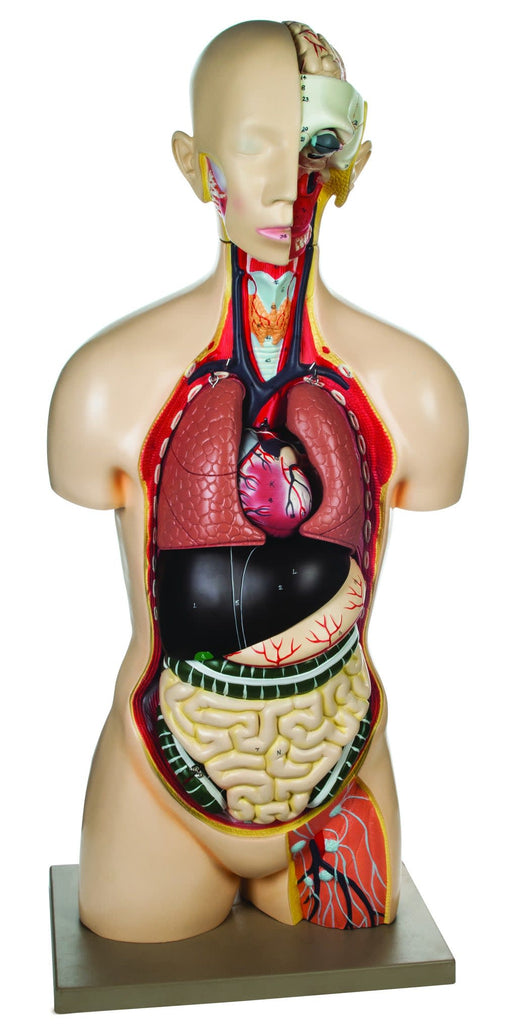

Model, Human, Open Back Toroso, Dual Sex, 27 Parts

Life size Dual Sex Excellent detail 33 inches tall Life size human torso is an excellent tool for anatomy studies. It features a dissected head t...

View full detailsAM11AAS -